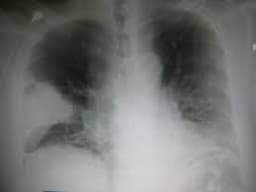

Contributor: Peter Bakes, MD

Educational Pearls: